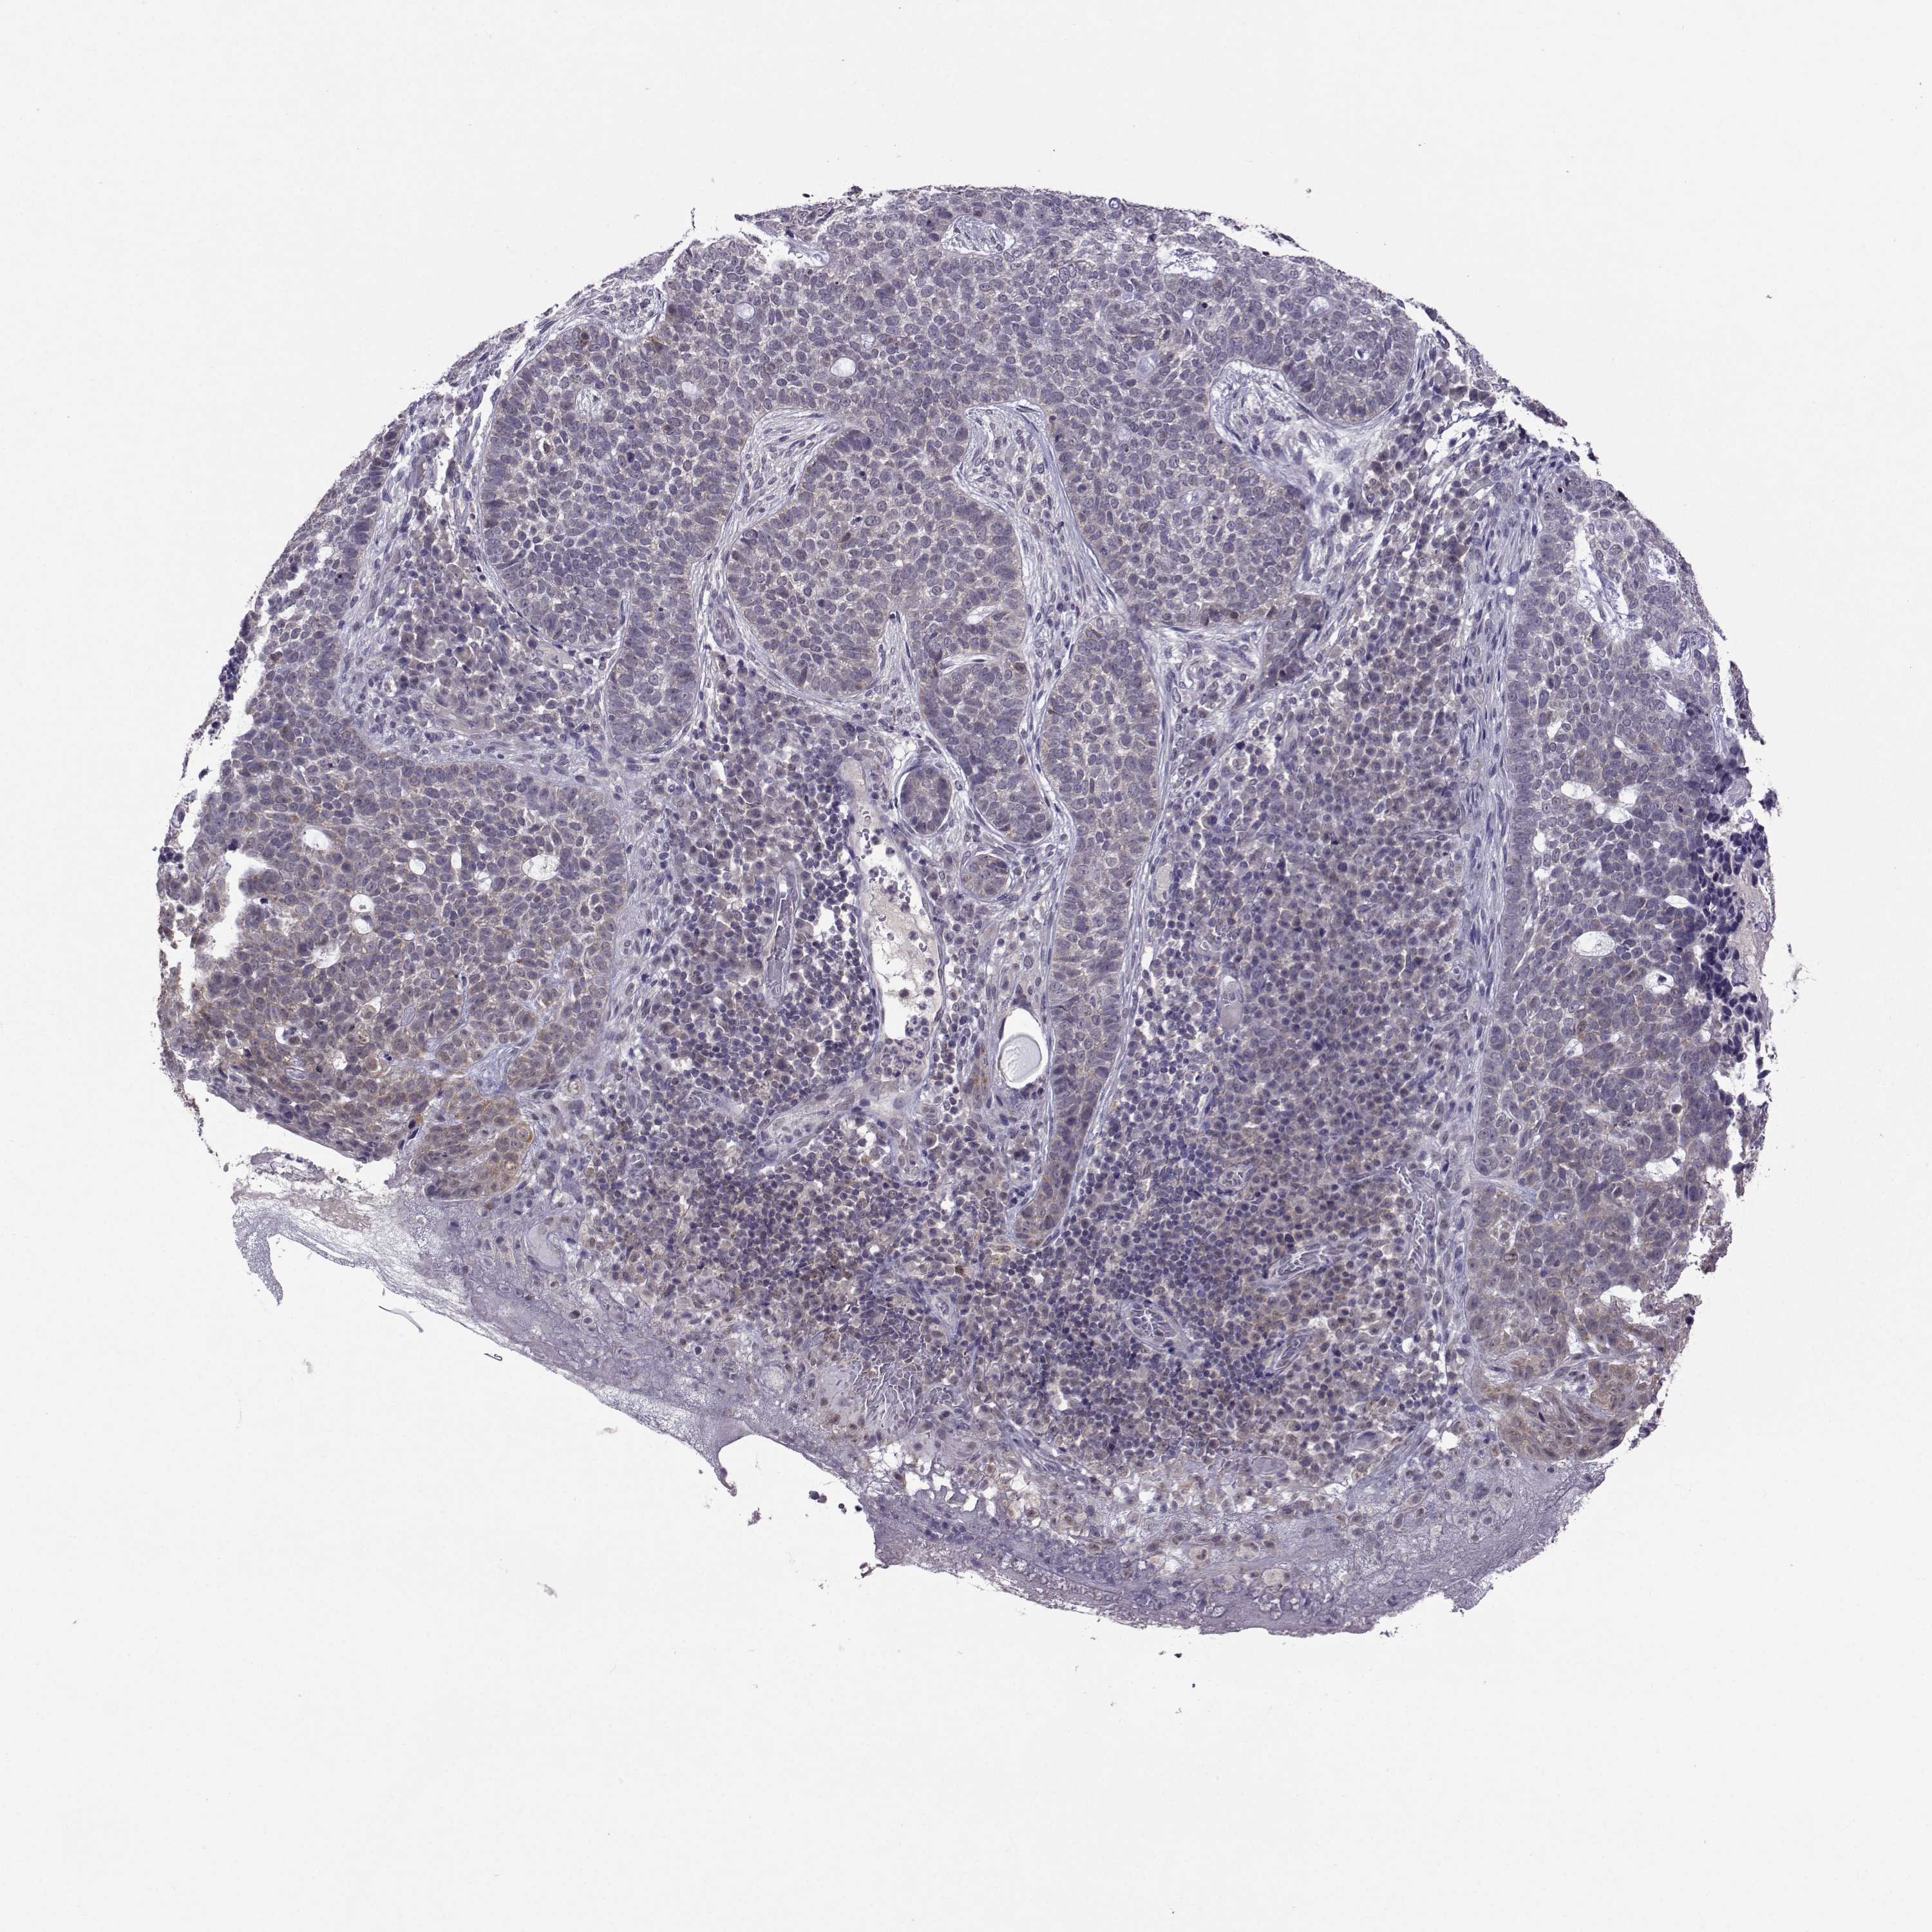

Basal cell and squamous cell cancer

SKIN CANCER - Protein expressioni

A mouse-over function shows sample information and annotation data. Click on an image to view it in a full screen mode. Samples can be filtered based on level of antibody staining by selecting one or several of the following categories: high, medium, low and not detected. The assay and annotation is described here.

Antibody stainingi

Antibody staining in the annotated cell types in the current human tissue is reported as not detected, low, medium, or high, based on conventional immunohistochemistry profiling in selected tissues. This score is based on the combination of the staining intensity and fraction of stained cells.

Each image is clickable and will lead to virtual microscopy that enables deeper exploration of all samples and also displays staining intensity scores, fraction scores and subcellular localization as well as patient and tissue information for each sample.

Antibody HPA005516

Antibody CAB015427

Basal cell carcinoma

Squamous cell carcinoma, NOS